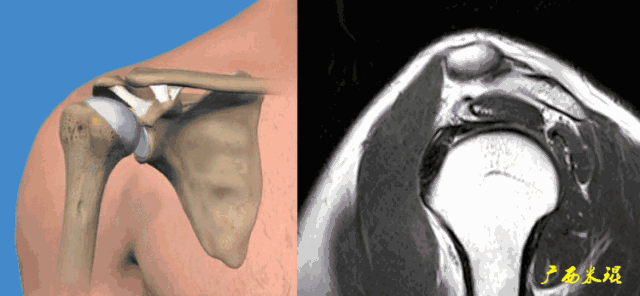

2、斜矢状位:垂直于冈上肌长轴,观察肩峰形态及喙肩弓,观察肩袖4个组分的短轴断面。

3、轴位:平行于关节盂/垂直于盂肱关节,主要评估盂唇,同时兼顾肩胛下肌、冈下肌及小圆肌。